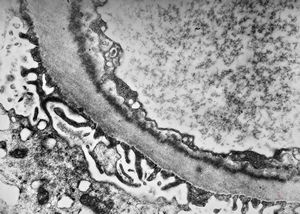

M,17y. | Alport syndrome - split and laminated basement membranes